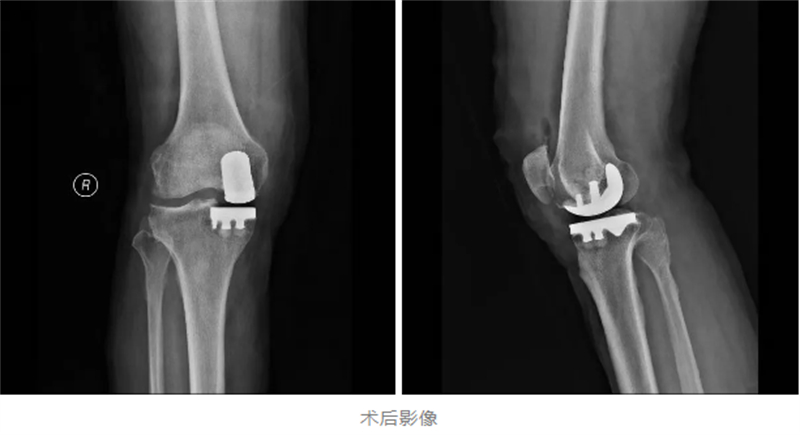

经过详细检查,关节骨病科副主任韦健博士诊断杨先生为重度骨关节炎。鉴于患者疼痛集中于膝关节前内侧,建议采用损伤小、恢复快的膝关节单髁置换术。“单髁置换就像给磨损的鞋底更换前掌,通过替换病变软骨面,更多保留正常关节组织。” 韦健博士解释道。

为确保手术安全与术后快速康复,关节骨病科与麻醉科展开深度协作,精心制定了个性化的麻醉方案和手术计划。手术中,采用了“超声引导下区域神经阻滞”加“全麻”的方式,既确保了手术过程中的无痛和舒适,又减少了麻醉对患者的副作用。手术当天,多学科团队配合默契,仅用1小时便顺利完成了置换手术。